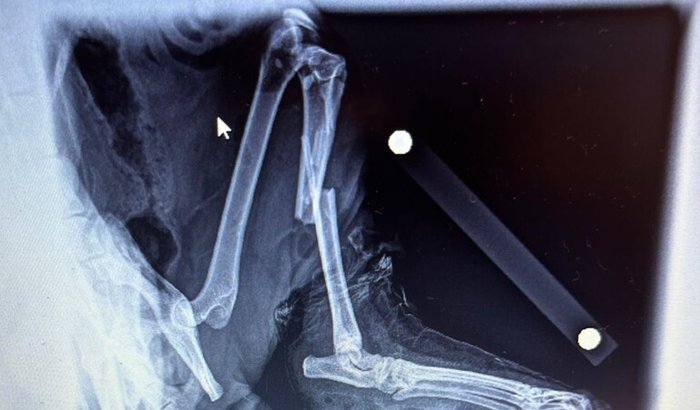

O Gato Amarel , sofreu maus tratos e quebrou a perna,   está  vakinha  visa custear os meticamentos  e exames pre- operatorios. ver tudo

O Gato Amarel , sofreu maus tratos e quebrou a perna,   está  vakinha  visa custear os meticamentos  e exames pre- operatorios.